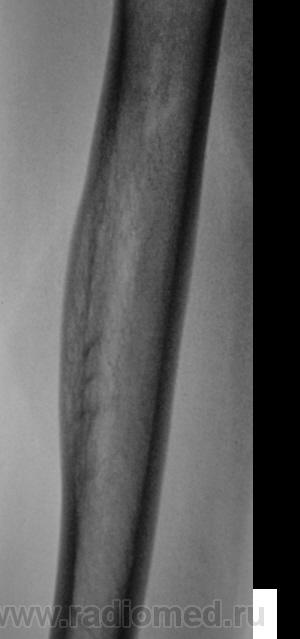

Да, в таком возрасте заподозрить хронику и неврологию не с руки (но все-таки исключить надо). В таком случае надо вторую (боковую) проекцию сделать.

Боковая проекция добавлена.

Изображения в боковой проекции с увеличением.

А что это за поперечные линии - костной перестройки, что ли?

Мне кажется, есть локальная слоистость кортикального слоя. Надо бы спросить ту, имя которой я поклялся не упоминать.

Неоднозначно всё